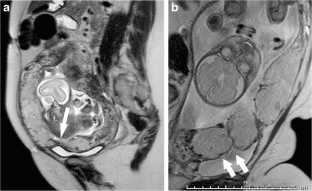

Fig. 1

Fig. 2

Fig. 3

Fig. 4

Fig. 5

Fig. 6

Fig. 7

Fig. 8

Fig. 9

Fig. 10